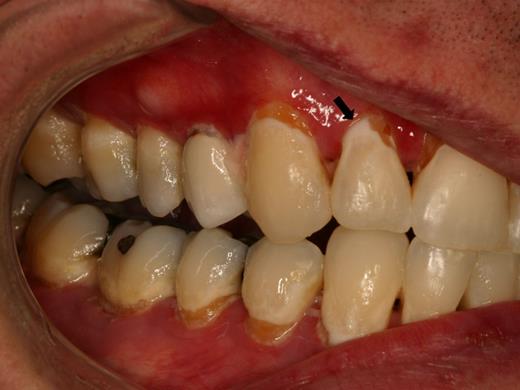

Patients with salivary gland cGVHD are at risk for developing secondary infectious complications because of diminished anticariogenic and antifungal activities. In addition to the effects on teeth (Figure 7), patients are at significant risk for recurrent oral candidiasis, especially if there is ongoing topical corticosteroid therapy for management of mucosal cGVHD, which suppresses mucosal immunity (see “Infections”; Figure 8).

Rampant cervical dental caries affecting all of the teeth in a patient with cGVHD of the salivary glands. Demineralization changes (arrow) appear chalky white.

Dental caries

Patients with salivary gland cGVHD are at risk for developing secondary infectious complications because of diminished anticariogenic and antifungal activities. The development of accelerated and often rampant dental caries is a largely under-recognized complication of oral cGVHD that can develop rapidly, leading to extensive dental treatment, extraction of teeth, and significant social and economic costs.65-67 Before the development of frank carious lesions, the teeth may demonstrate demineralization changes along the cervical margins, characterized by a white and chalky appearance (Figure 7). Dental caries tend to develop at the cervical margins and interproximal surfaces where dental plaque accumulates because of lack of salivary flow. Exacerbating this problem is that patients with oral mucosal cGVHD may neglect oral hygiene because of discomfort associated with tooth brushing, compounding the effects of salivary gland changes. In addition to the effects on teeth, patients with salivary gland cGVHD are at significant risk for recurrent oral candidiasis, especially if there is ongoing topical corticosteroid therapy.